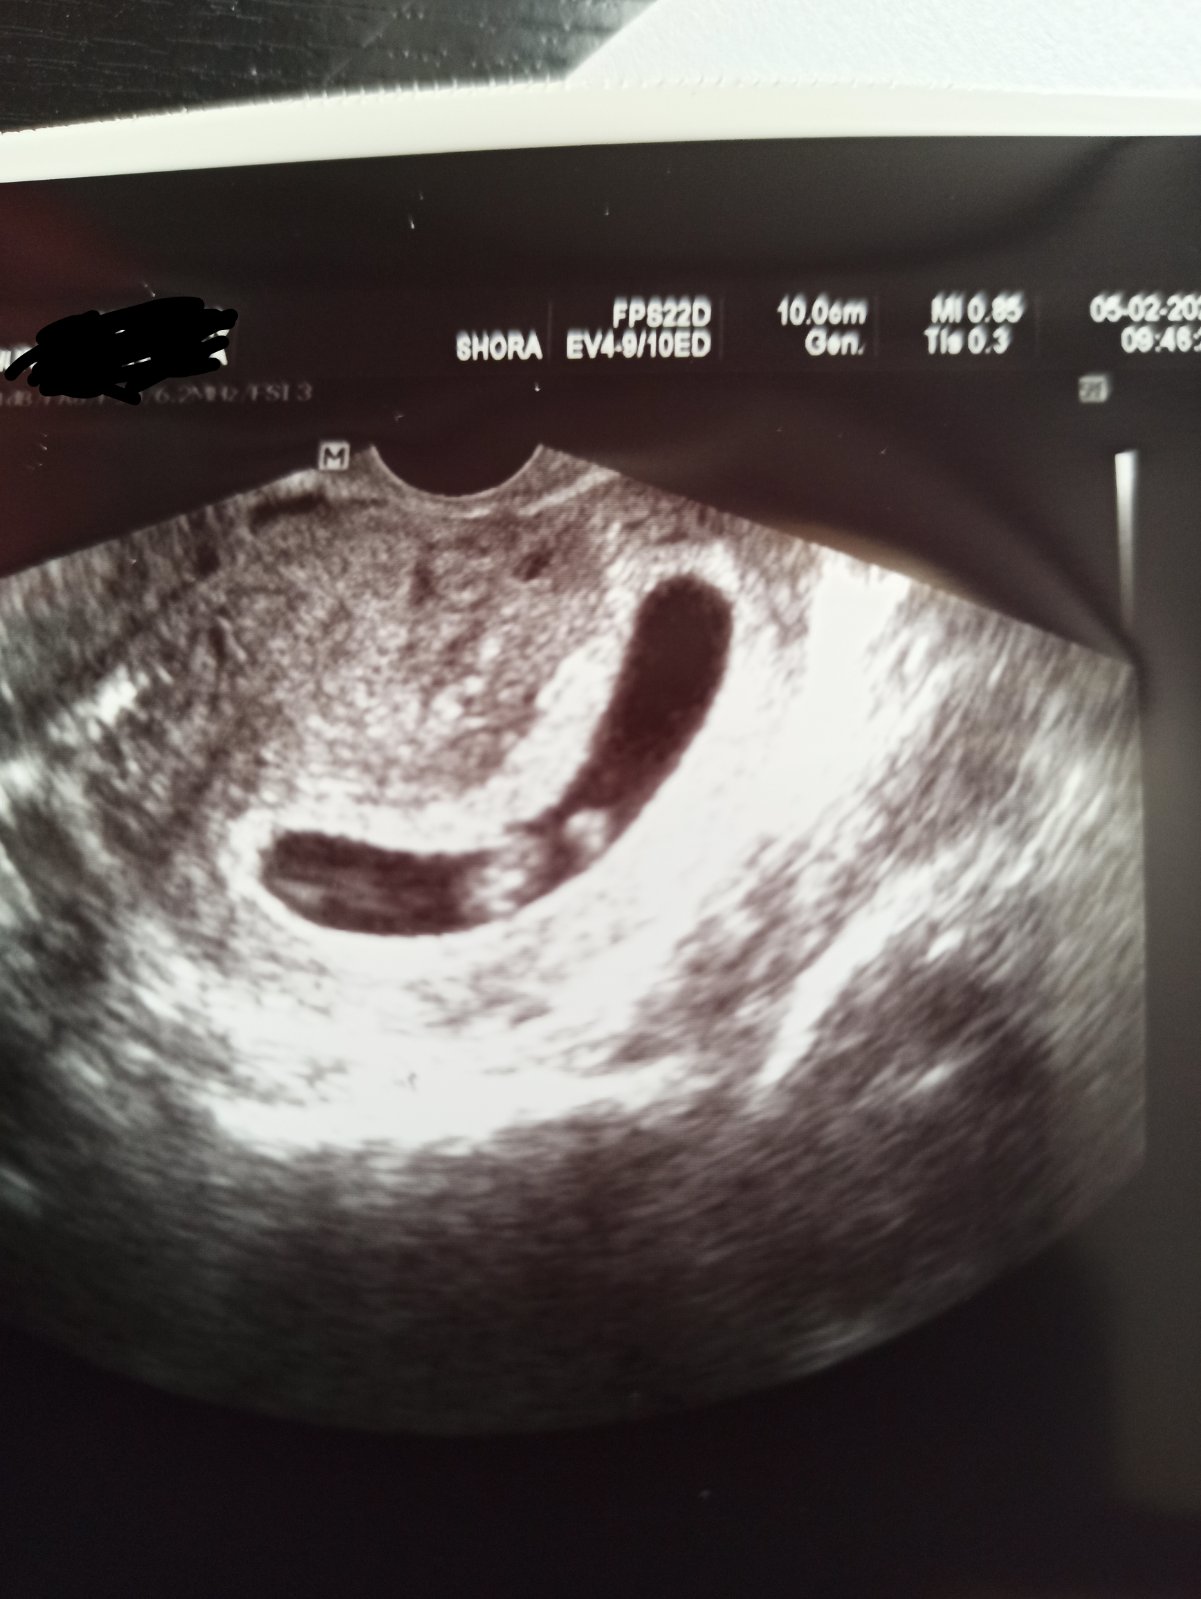

Tady jsou fotky 🙂